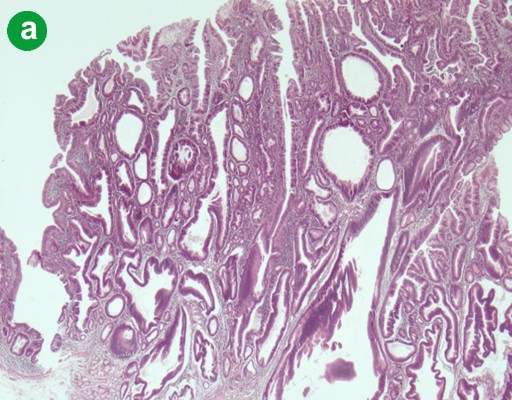

A pancreaticoduodenectomy was performed, showing an exophytic duodenal tumor invading the ampulla of Vater, measuring 4.5x5.0 centimeters. At the center of this tumor, a well delineated red-brown nodule measuring 12 mm was observed (Figure 1b). Microscopic examination identified two distinct tumor cell populations. The first one corresponded to an exocrine high grade tubulo-villous adenoma largely extending onto the external part of the ampulla and to the duodenal mucosa (Figure 2a). An area of well-differentiated adenocarcinoma was identified inside the adenoma, measuring 6 mm, infiltrating the duodenal submucosa but sparing the muscularis propria (Figure 2b). The second tumor cell population was of endocrine type. It formed a well-delineated central nodule of 1 cm, sharply demarcated from the exocrine component (Figure 2c). It was composed of cords or acini of well-differentiated endocrine cells combined with psammoma bodies (Figure 2d). Endocrine cells contained regular nuclei, and granular and eosinophilic cytoplasm. Mitotic activity was low (less than 2 mitoses per 10 high-power fields). Immunohistochemical analysis demonstrated positive and diffuse staining of the endocrine component with antibodies directed against the neuroendocrine markers synaptophysin and CD56 and with anti-somatostatin antibody (Figure 2e). Chromogranin A was negative. The proliferation index, evaluated using MIB-1 antibody according to the TNM classification [1] was calculated at 2%. The main pancreatic duct was invaded by the adenomatous high grade component, but the secondary ducts and biliary duct did not display any dysplasia or malignant features. The infiltrating tumors did not extend into the pancreatic parenchyma. Lymph node dissection revealed 6 metastatic nodes: 3 were metastatic from the adenocarcinoma component and 3 from the endocrine carcinoma (Figure 2f).

Figure 2. a. The high grade tubulo-villous adenoma extending to the duodenal mucosa (H&E staining, x200). b. An area of well differentiated adenocarcinoma infiltrating the duodenal submucosa (H&E, x400). c. The endocrine component (small arrows) is located under the exocrine high grade adenoma (large arrow) (H&E, x100). d. The endocrine component is well differentiated and contains psammoma bodies (arrows) (H&E, x400). e. Endocrine tumor cells abundantly and diffusely expressing somatostatin (immunostaining with somatostatin antibody, counterstained with hematoxylin; x 200). f. Metastatic lymph nodes are present, either from the exocrine (left) or the endocrine (right) component (H&E, x100). |